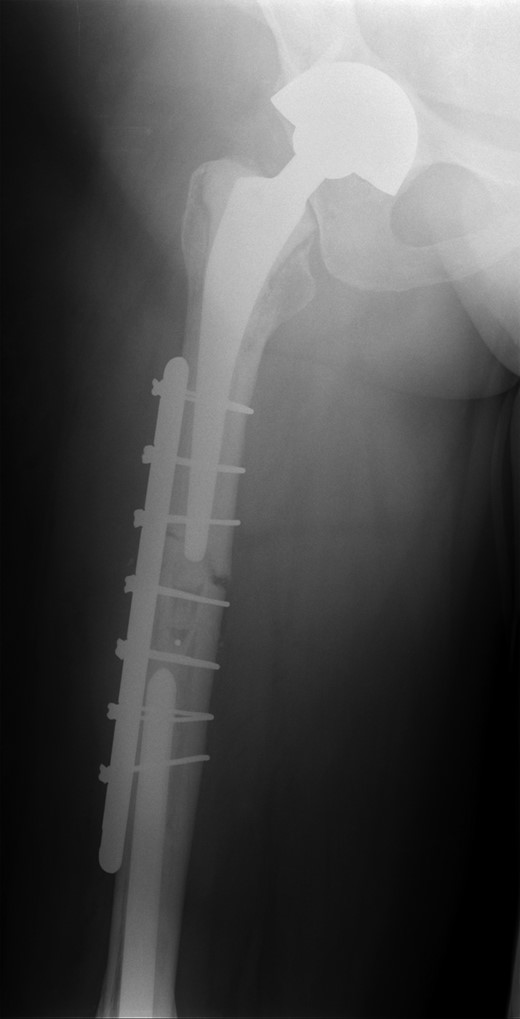

She subsequently sustained a periprosthetic fracture at the distal tip of her right total hip replacement (Fig. 1). An initial attempt was made to manage this fracture with a plate and Dall-Miles cables (Fig. 2); however, the fracture did not unite. The patient went on to have a custom-made cement-linked internal proximal femoral replacement, which had a hollow cylindrical design to accept the stem of the existing well-fixed distal femoral component (Figs 3 and 4). This linked prosthesis effectively converted her separate prostheses to a total femoral replacement, sparing her distal femoral replacement from revision. She had no problems postoperatively and recovered well from her surgery.

Custom-made cement-linked internal proximal femoral replacement.

Existing distal femoral replacement with stem linked to custom-made internal proximal femoral component visible in upper half of the image.